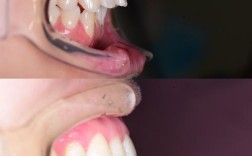

- 问题:上颌前突,侧颜“凸嘴”,不敢大笑;

- 方案:拔除4颗前磨牙+隐适美隐形矫正;

- 效果:矫正1年8个月,牙齿排齐,龅牙改善,侧颜线条自然,自信心提升;